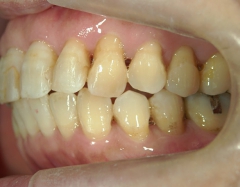

全顎ワイヤー矯正 症例(6

)

58歳女性 浜松市浜北区

在住

治療期間11

ヶ月